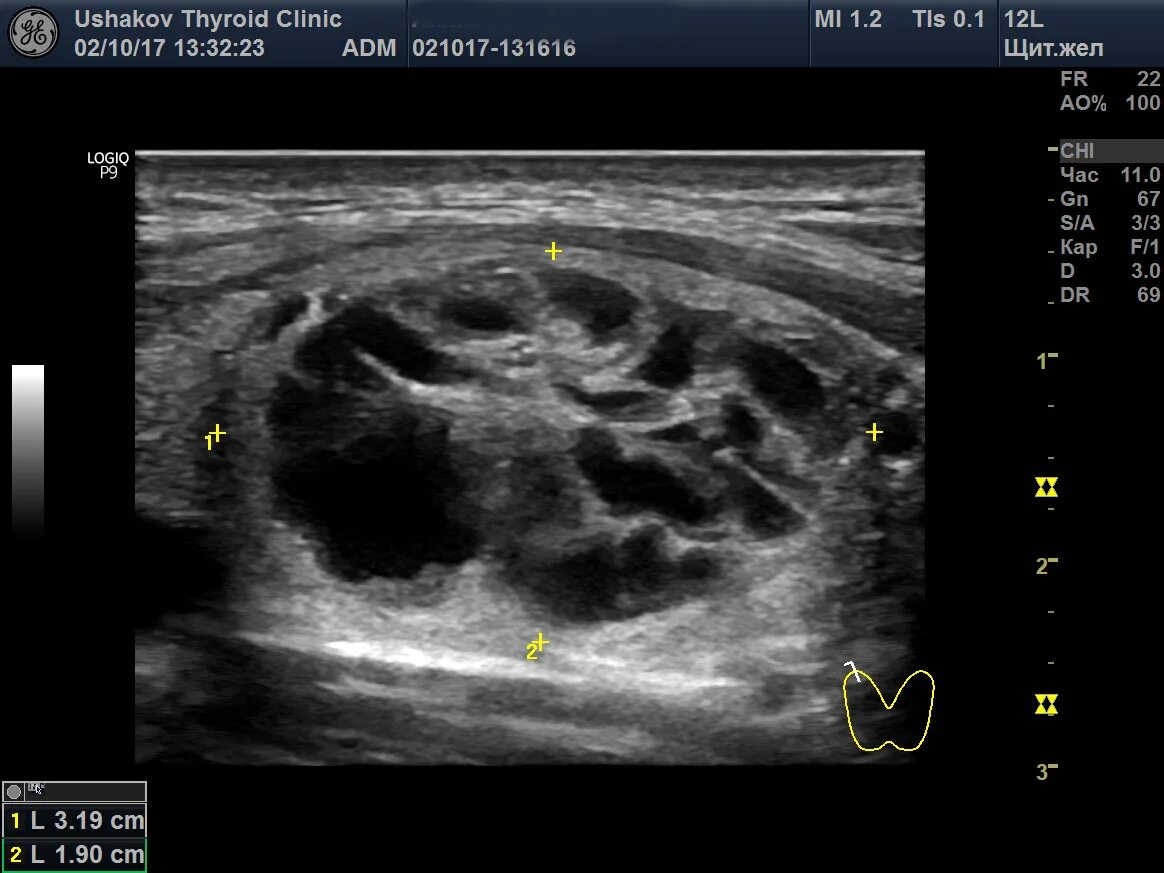

Диффузные изменения щитовидной железы на узи